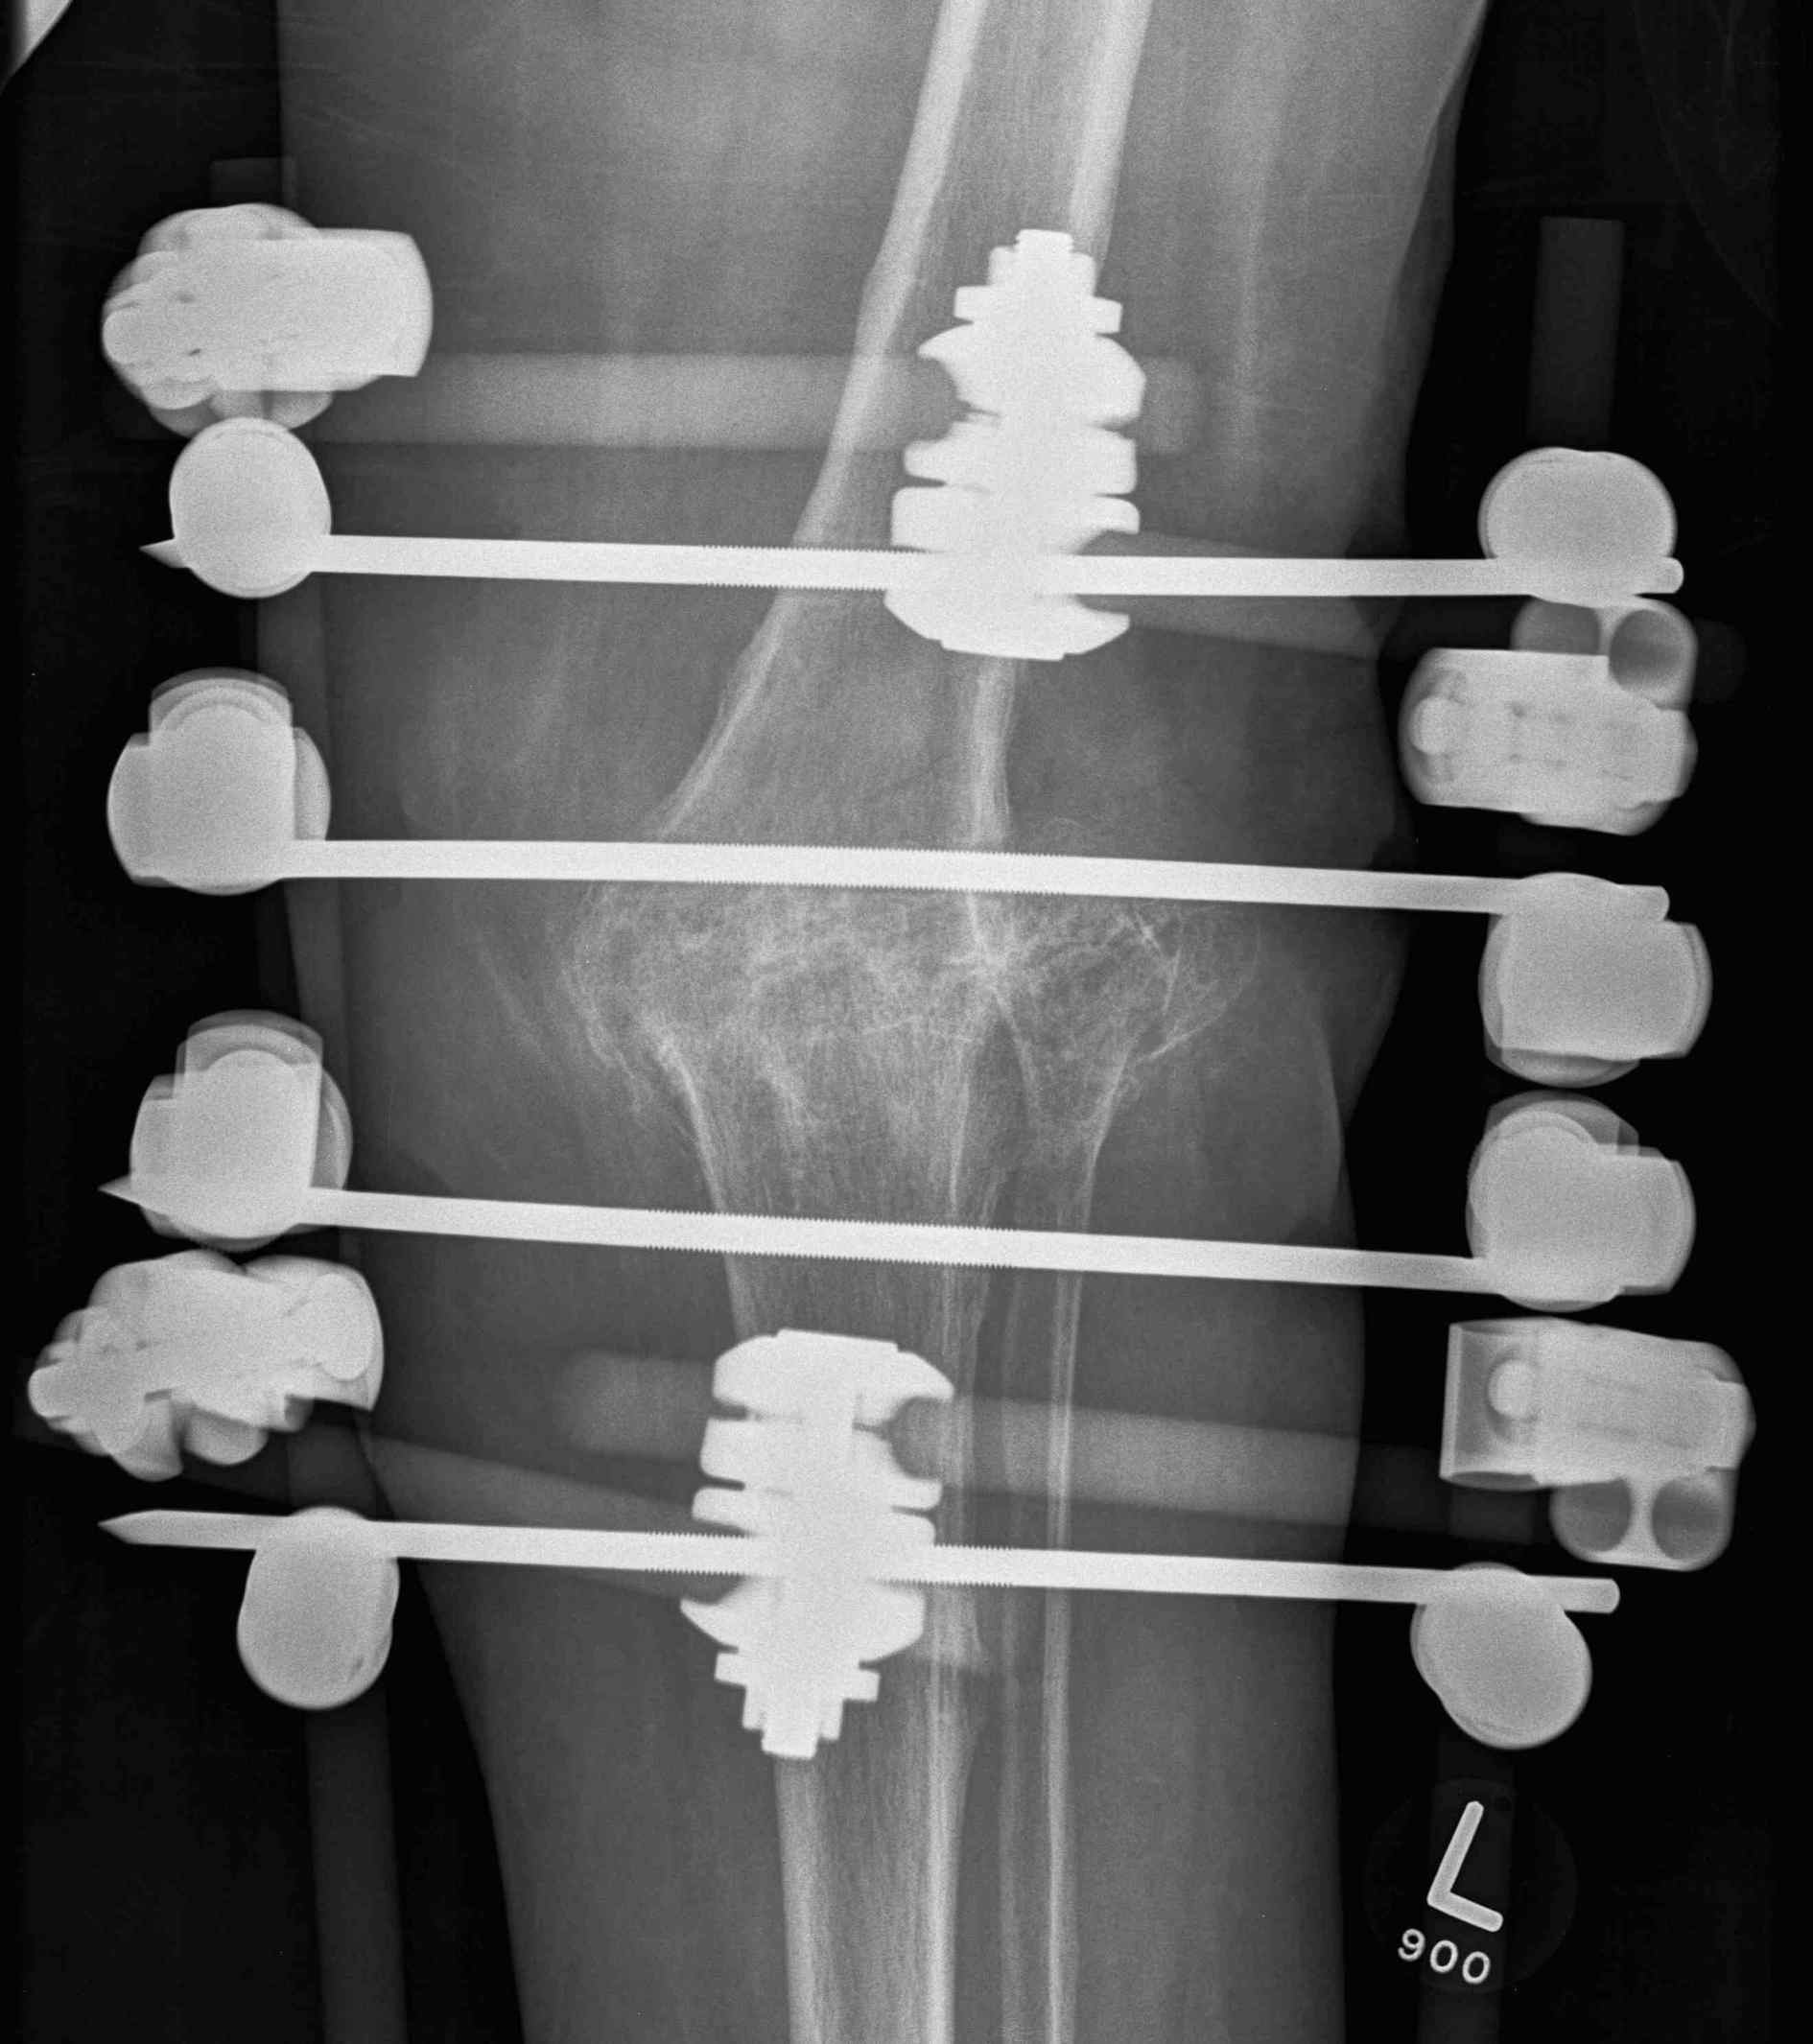

3. External fixator

External Fixation

Results

Corona et al. Eur J Orthop Surg Traumatol 2020

- 29 cases end stage infected TKA

- biplanar external fixation eradicated infection and obtained union in 100% at 5 months

- uniplanar external fixation eradicated infection in 86% and obtained union in 81% at 10 months